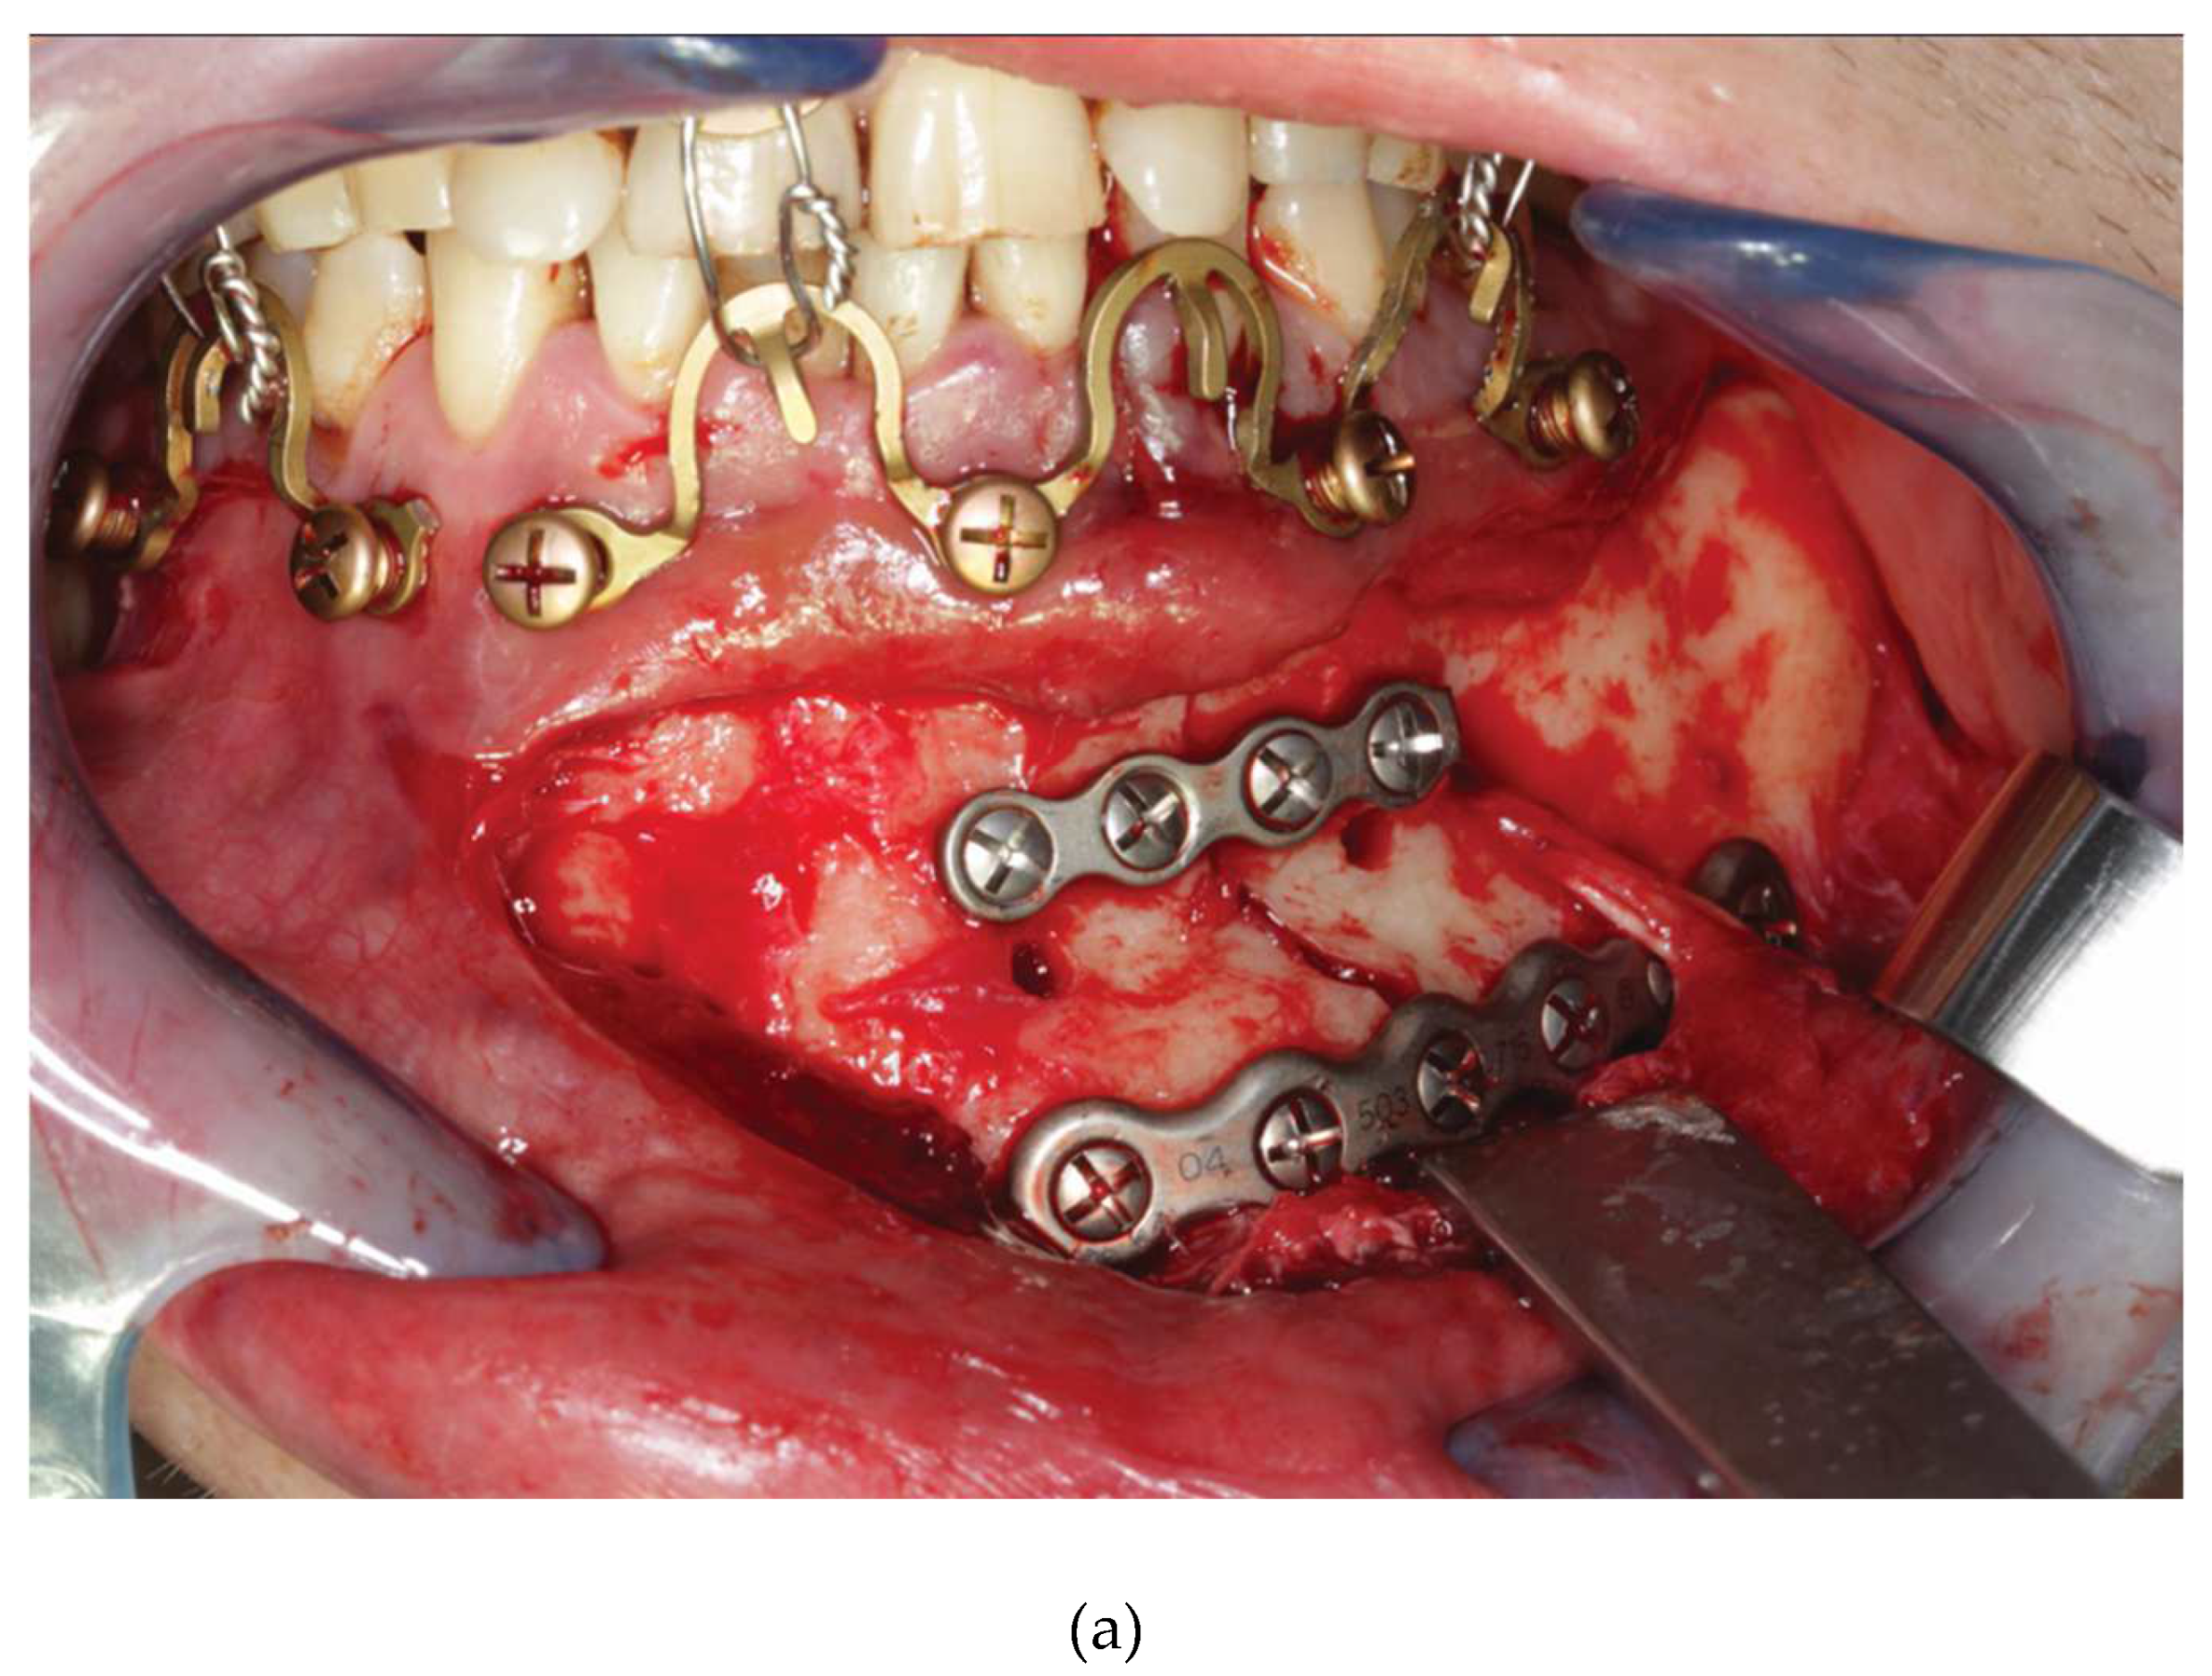

Figure 16.

Figure 16 A: Case with a double mandibular fracture – right mandibular angle; left condylar base (see panoramic x-ray in

Figure 16 L ). Deep bite not suitable for conventional tooth borne arch bars. A low profile MWP Omega segment is tried on along the mucogingival transition zone for interradicular screw fixation in the premolar region of the left maxilla. Interferences with the habitual occlusal position and / or articulatory movements must be ruled out.

Figure 16 B: Owing to the more comfortable access the anterior screw is inserted first. Angulation of the screw should be avoided. The conical locking head of the screw should not get engaged into the plate hole prematurely.

Figure 16 C: The posterior screw is turned likewise halfway into the bone for a loose prefixation of the MWP segment.

Figure 16 D: The MWP segment is supported with a Freer elevator as a spacer below the flatbed portion and the screws are tightened alternately until the plate segment is firmly gripped by the locking threads.

Figure 16 E: Screw fixation of MWP segment completed. Most of the time the conical locking head cannot be fully countersunk in the plate hole. It is essential, however, that the threads of the plate hole and the locking threads of the screw effectively purchase.

Figure 16 F: High profile MWP Omega segment adapted to the interradicular spaces in the premolar region of the opposite jaw, in this case the left mandible. Interferences with the habitual occlusal position and / or articulatory movements must be ruled out.

Figure 16 G: Prefixation – plate segment still moveable.

Figure 16 H: Posterior screw turned into the plate hole, supporting the plate with a Freer elevator from underneath.

Figure 16 I: Anterior screw turned in, while plate segment is supported with Freer elevator - alternate tightening of the screws.

Figure 16 J: MWP segment finally fixed in juxtaposition to the vestibular tooth crowns just below occlusal plane. A steep canine guidance, however, averts disruptive contacts between the second upper premolar and the top rail of the plate.

Figure 16 K: MWP Omega segments mounted in all jaw quadrants for temporary intraoperative MMF with wire ligatures to immobilize the mandible. Note: Conical locking heads are partially countersunk, only.

Figure 16 L: Postoperative Panoramic x-ray after transoral ORIF (miniplate osteosynthesis). 4 MWP segments left in place for optional functional treatment during follow-up. All screws for MWP attachment located in interradicular alveolar bone Inset: four MWP Omega segments as oriented and used in this illustrative case.

Source/origin of Figure 16 A – L : Photograph collection – C.P. Cornelius